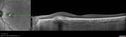

Pattern Dystrophy - Adult Vitellifrom (Best)448 views71 year old female - lesions nasal to the fovea in both eyes. (20/40 OU)00000

Pattern Dystrophy - Adult Vitellifrom (Best)408 views71 year old female - lesions nasal to the fovea in both eyes. (20/40 OU)00000

Pattern Dystrophy - Adult Vitellifrom (Best)436 views71 year old female - lesions nasal to the fovea in both eyes. (20/40 OU)00000

Pattern Dystrophy - Adult Vitellifrom (Best)484 views71 year old female - lesions nasal to the fovea in both eyes. (20/40 OU)00000